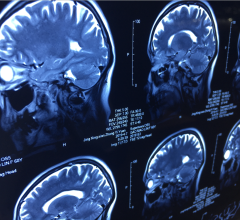

May 19, 2022 — Brainlab announced that clinicians at UZ Brussel are the first to treat patients with the company’s new ...